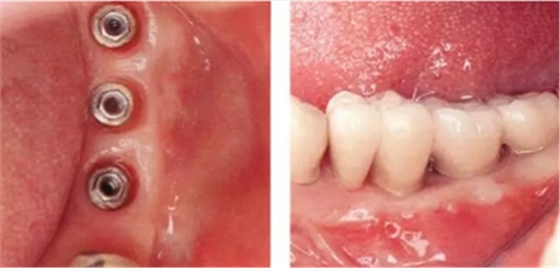

▲圖8-1,2

圖8-1 缺損牙槽嵴的頰側幾乎沒有角化齦。

圖8-2 (牙合)面照。從牙槽嵴到舌側的區(qū)域內有一定程度的角化齦,但是角化齦寬度不足。(Type2-Class2)。

▲圖8-3,4

圖8-3 在腭側采集移植片,然后在頰側進行FGG。

圖8-4 將原有的舌側角化齦移向根尖側,以增大角化齦。

▲圖8-5,6

圖8-5 佩戴上部基臺時的(牙合)面照。獲得了充足的角化齦。

圖8-6 佩戴最終修復體時的(牙合)面照。